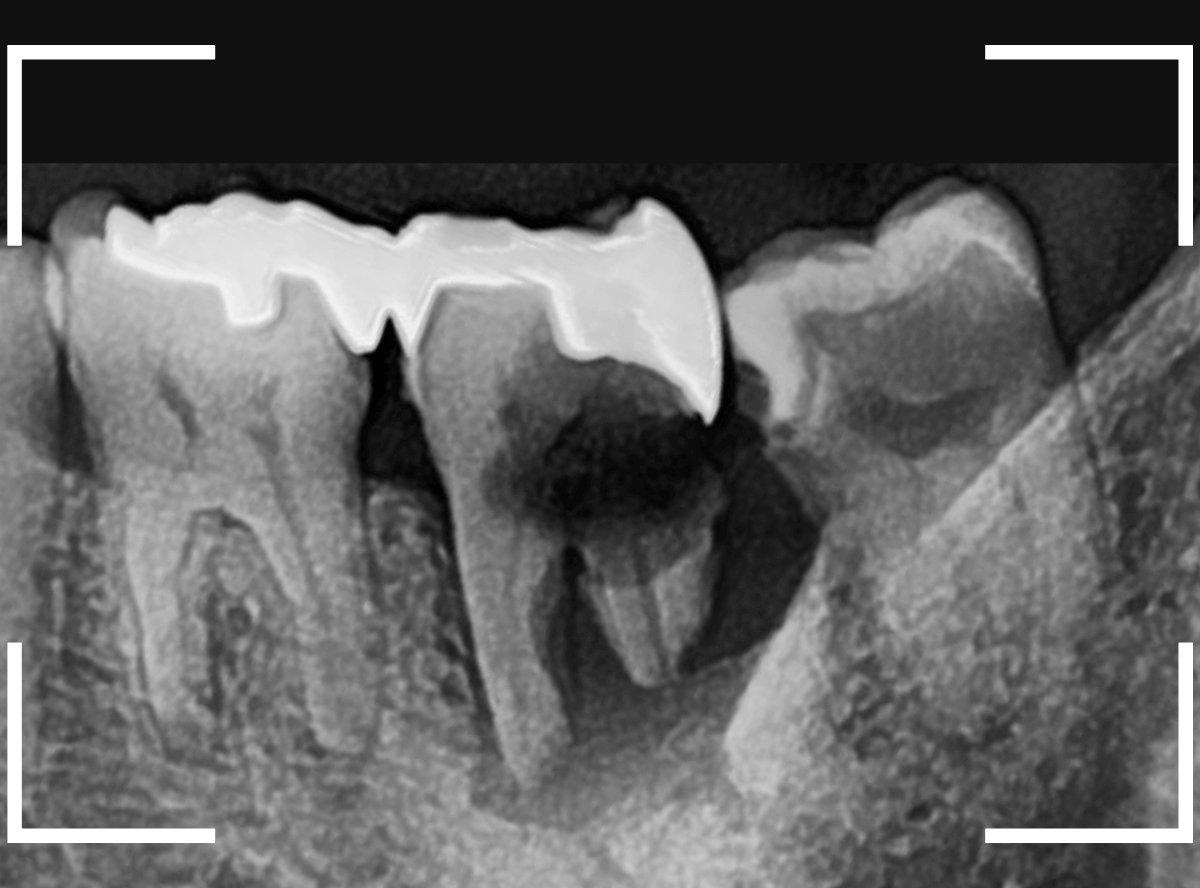

レントゲン写真で確認します。

一つ手前の歯も大きな虫歯で根元までボロボロです。

これではどちらが痛みの原因になってもおかしくありません。